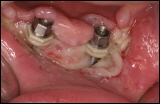

Implantatlockerung/ Implantatverlust

Nach dem Einbringen eines Implantates beginnt die sogenannte Einheilphase, die in der Regel zwischen zwei bis fünf Monate lang dauert. Sie ist die kritische Phase, weil in dieser Zeit die meisten Implantate verlorengehen. Eine Implantatlockerung kurz nach dem Einsetzen eines Implantates kann zwei unterschiedliche Ursachen haben. Zum einen eine zu geringe Primärstabilität (primärer Halt des Implantates selbst) im Zusammenhang mit einem Knochenaufbau. Das bedeutet, dass das Implantat im ortsständigen noch vorhandenen Knochen nicht ausreichend Halt findet. Vergleichen wir es mit eine Schraube in einer Wand. Während eine 3 cm lange Schraube in einer 1 cm dicken Wand zwar auf der anderen Seite herausguckt, hat sie in der Wand dennoch soviel Stabilität, dass sie sich selbst halten kann. In einer papierdünnen Wand dagegen ist der Halt selbst für das Gewicht der Schraube nicht mehr ausreichend, sie ist mobil.

Zum anderen können heftige entzündungsbedingte Knochenabbauprozesse dazu führen, dass ein vorerst fest sitzendes Implantat locker wird. Die Ursache hierfür ist eine Schädigung des Implantatlagers beim Aufbereiten des Bohrlochs durch starke Hitzeentwicklung. Diese kann auftreten bei

Trotz schonensster Aufbereitung des Implantatlagers (Bohrlochs) bleibt eine minimale Schädigung von Knochenstrukturen nie aus. Daher ist bei einer Implantatlockerung nicht zwangsläufig auf einen ärztlichen Fehler zu schließen. Es muss von Fall zu Fall entschieden werden, ob das Implantat entfernt werden muss oder aber die Möglichkeit einer Festigung besteht. Wenn das Implantat entfernt wird, sollte 6-8 Wochen gewartet werden, bis an dieselbe Stelle erneut ein Implantat eingebracht wird.

In seltenen Fällen kann sich bei der offenen Einheilung (d.h. das Implantat heilt also nicht unter der geschlossen Schleimhaut ein, sondern ragt mit der Schulter in die Mundhöhle) die Abdeckschraube (Verschlussschraube) lösen. Dies führt nicht selten zu einer verständlichen Beunruhigung des Patienten, weil er glaubt, dass ganze Implantat sei locker. Ein wieder Festschrauben der Kappe durch den Implantologen löst in Sekundenschnelle das Problem.